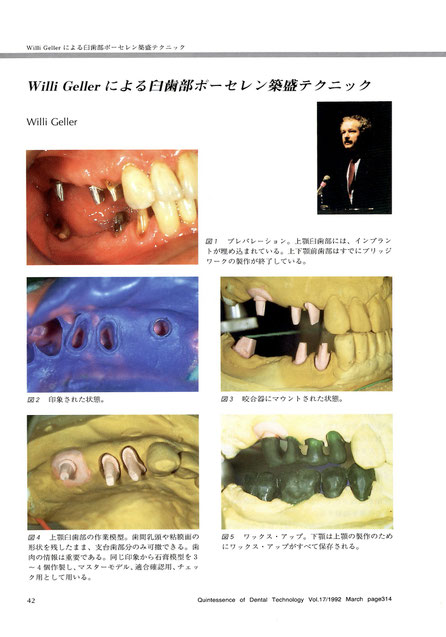

図1 プレパレーション。上顎臼歯部には、インプラントが埋め込まれている。上下顎前歯部は既にブリッジワークの製作が終了している。

図2 印象された状態。

図3 咬合器にマウントされた状態。

図4 上顎臼歯部の作業模型。歯間乳頭や粘膜面の形状を残したまま、支台は部分のみ可撤できる。歯肉の情報は重要である。同じ印象から石膏模型を3〜4個作製し、マスターモデル、適合確認用、チェック用として用いる。

図5 ワックス・アップ。下顎は上顎の製作のためにワックス・アップが全て保存される。